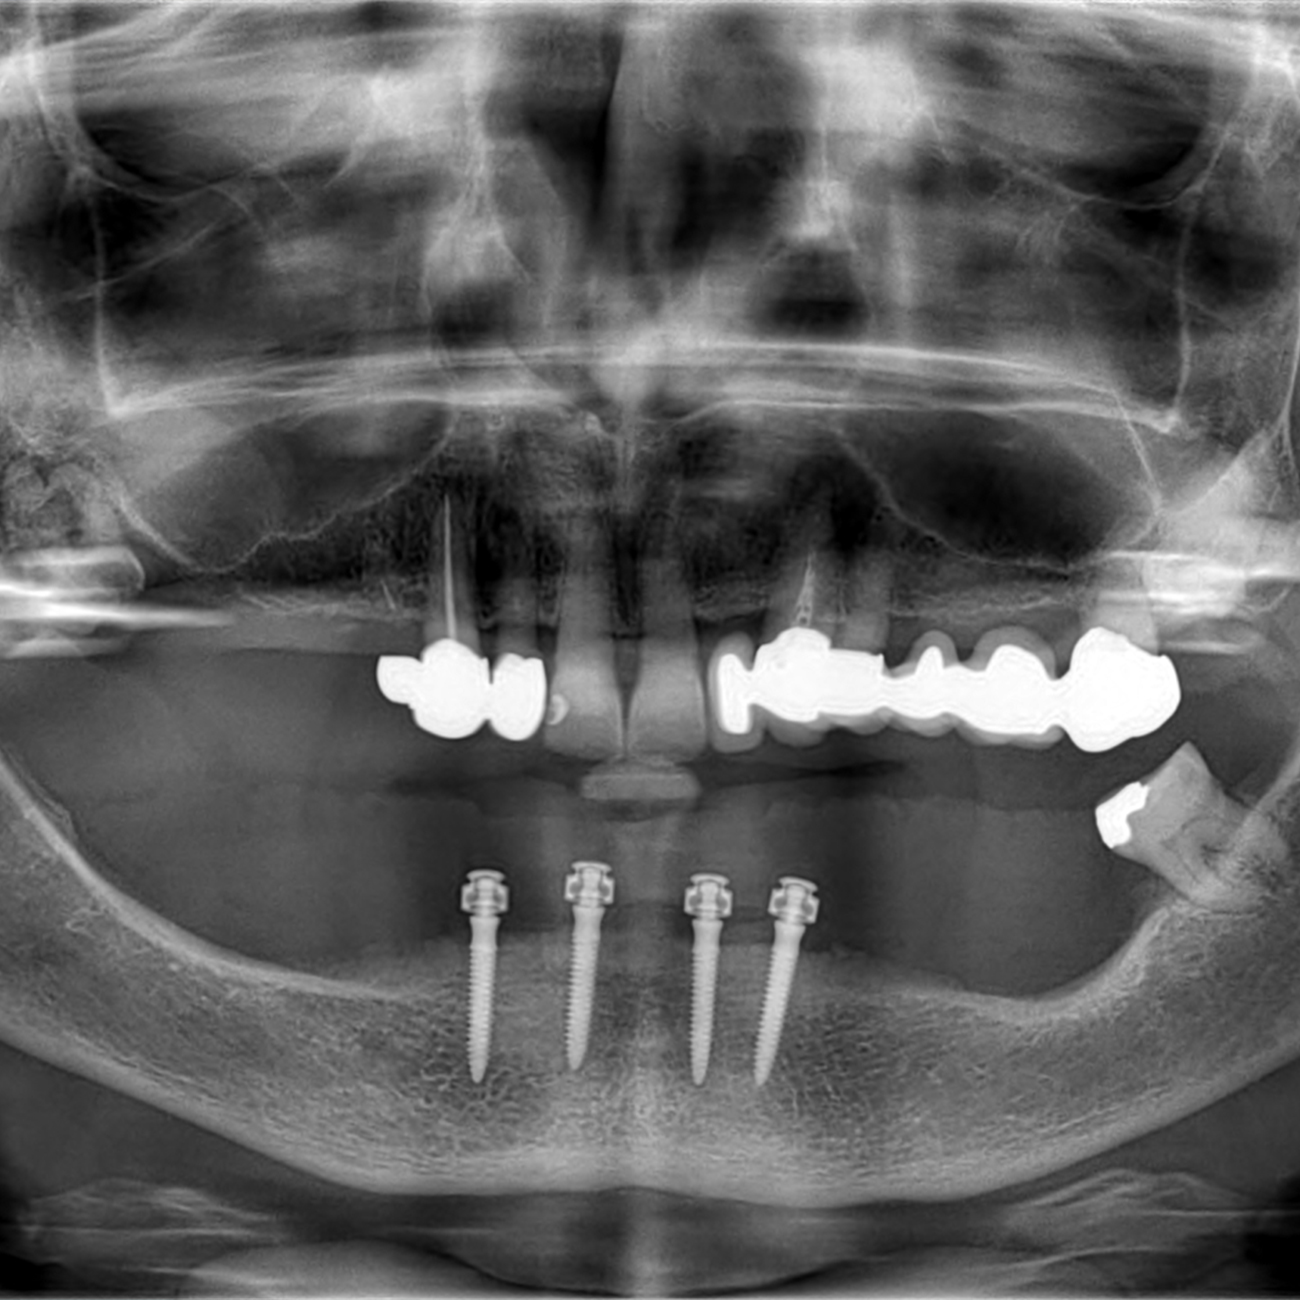

Protesi avvitata per arcata inferiore: Metodo All On 4

Un paziente edentulo richiede dentatura fissa. La pianificazione del trattamento avviene con supporto di TAC CONE BEAN, la quale permette di progettare virtualmente l intero trattamento e di mostrare al paziente virtualmente la posizione implantare e protesica. Mediante la realizzazione di una mascherina chirurgina in un'unica seduta si esegue la chirurgia implantare; successivamente viene realizzata una protesi che viene avvitata direttamente nella bocca del paziende e rimane quindi fissa.